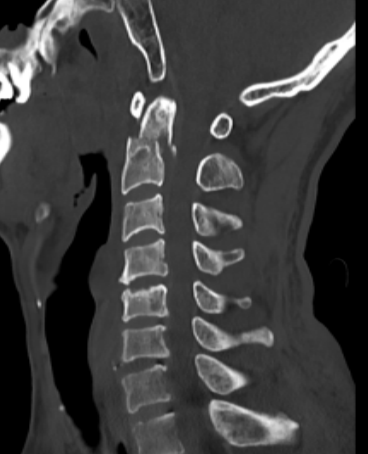

患者刘某某今年50岁,因不慎摔伤导致颈部疼痛、活动受限,并伴有双侧上肢无力、麻木,到泉港总医院做了急诊颈椎CT检查,报告为“枢椎齿状突骨折伴寰椎椎体后脱位”,随即收入院治疗。

入院后,福建医科大学附属第一医院下派脊柱外科专家朱希田副主任医师立即查看了患者的病情,考虑患者枢椎齿状突骨折伴寰椎后脱位致高位颈脊髓损伤可能性较大,如果不尽早手术,将引起颈脊髓损伤继续加重,并可导致高位截瘫可能。朱希田副主任医师立即将病情汇报医院领导,开通核磁共振检查绿色通道,进一步明确患者病情。

后路寰枢椎内固定手术由于难度大、风险高,此前在泉港地区各医院尚未开展该项手术,该例手术病例为泉港地区首例。面对时间短、要求高的挑战,朱希田副主任医师一方面仔细研究阅读患者影像学资料,制定个体化置钉方案,同时积极准备手术相关器械,经过认真充分的术前准备,患者于入院后第3天进行手术。